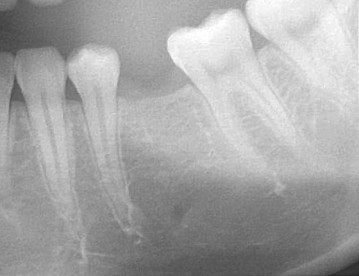

患者許小姐,左下第二小臼齒,因為深度蛀牙,因而牙齒被拔除(圖一、圖二、圖三),患者由於是一位高二學生,深怕缺牙久了若不處理,鄰牙可能倒過來(圖四),但若以傳統假牙修復,還需再磨完整的自然牙(圖五),經轉診至本診所尋求人工植牙。

圖一 |